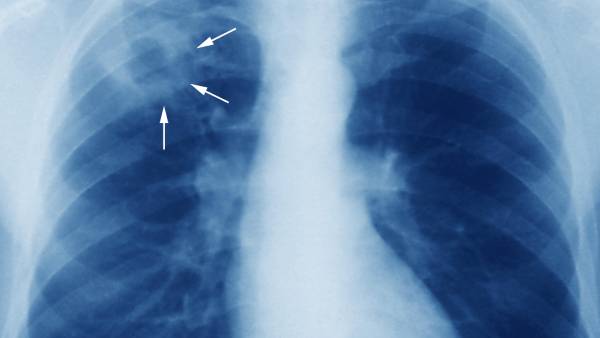

மாஸ்க் அணிவது, கைகளை அடிக்கடி கழுவி சுத்தமாக வைத்துக் கொள்வது போன்ற நடவடிக்கைகள் மூலம் மற்ற சுவாசப் பிரச்சினைகள் பெருவாரியாகக் குறைந்துள்ளன. ஆனால் மற்ற நோய்களுடன் ஒப்பிடுகையில் காசநோய் பாதிப்பு கம்கியான அளவே குறைந்துள்ளதாக மருத்துவர்கள் தெரிவிக்கின்றனர். காசநோயை ஏற்படுத்தும் பாக்டீரியாக்கள் மனிதனின் உடலில் இன்ஆக்டிவாக பல காலம் இருக்கும் என்பதால், காசநோய் பரவலைக் கட்டுப்படுத்துவது மிகவும் சிரமமான ஒன்று.